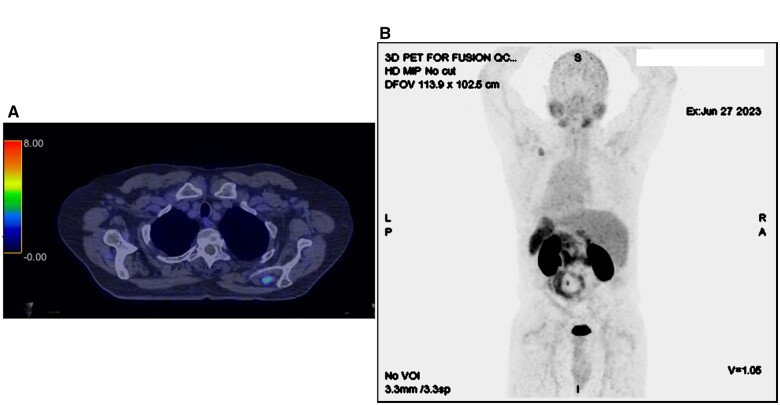

颗粒细胞瘤是一种罕见的、多为良性的软组织神经外胚层肿瘤,最常见于皮肤和周围软组织。迄今为止,还没有关于颗粒细胞瘤 PSMA-PET 阳性的出版物。在这名 60 岁的男性身上,对局部中危前列腺癌进行 PSMA-PET 分期治疗时意外发现了一个 PSMA 亲和性左上肌病变,随后经活检证实为颗粒细胞瘤。我们介绍了首例PSMA-avid颗粒细胞瘤病例,并补充了越来越多关于PSMA-PET在前列腺癌以外的良性和恶性病变中的avidity的文献。

Granular cell tumour is a rare, mostly benign, soft tissue, neuroectodermal tumour, most commonly seen in the skin and peripheral soft tissue. There are no publications to date of PSMA-PET avidity in a granular cell tumour. In this 60 year old male, staging PSMA-PET for a localized intermediate risk prostate cancer incidentally identified a PSMA-avid left supraspinatus lesion, which was subsequently biopsy-proven as a granular cell tumour. We present the first case of PSMA-avid granular cell tumour and add to the growing literature documenting PSMA-PET avidity in benign and malignant lesions apart from prostate cancer.